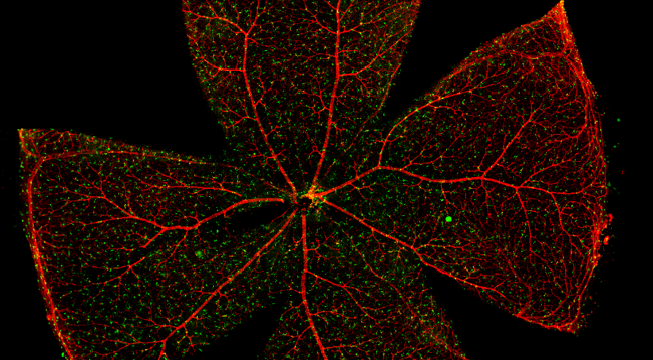

一般而言,眼底图像通常都是通过激光扫描成像进行采集,但是由于眼底可观测的视野往往是很有限的,一个患者的眼底信息需要多张扫描图像才能完全显示出来。这种局限性大大不利于病情进行全面的、细致的诊断。Tissue Cytometry全景组织流式定量分析技术进行全景图像获取,在单细胞、组织结构、细胞空间信息等多个层面进行定位、定性、定量分析。从而更好的对病变区域进行有针对性的跟踪观察和全面分析。

视网膜荧光样本中小胶质细胞胞体、神经纤维识别、血管识别、血管斑点识别、神经元与血管的距离分析。

1. 利用TissueFAXS系统进行玻片荧光的全景扫描。

2. 使用StrataQuest分析软件进行定量分析。

3. 根据FITC通道识别神经胞体并筛选出有效细胞胞体(细胞核识别算法)。

4. 膜识别FITC染色信号的区域确定神经纤维,并对不同长度神经纤维进行分类。

5. 识别血管的Texa Red染色区域面积及强度。

6. 计算神经元与血管间的空间距离,并统计数量和占比。

7. 根据毛细血管亮斑的识别结果,统计新生小血管数量。